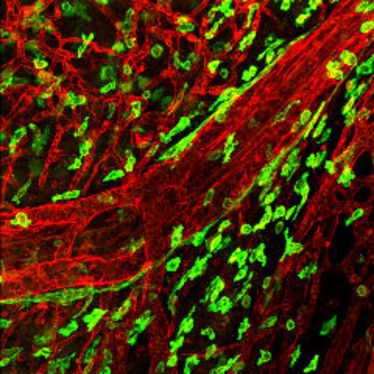

1. Small Animal Imaging Workshop in Münster

1. Small Animal Imaging Workshop in Münster

22.11.2010

- 26.11.2010

1. Small Animal Imaging Workshop in Münster

1. Small Animal Imaging Workshop in Münster

22.11.2010

- 26.11.2010

1. Small Animal Imaging Workshop in Münster

1. Small Animal Imaging Workshop in Münster